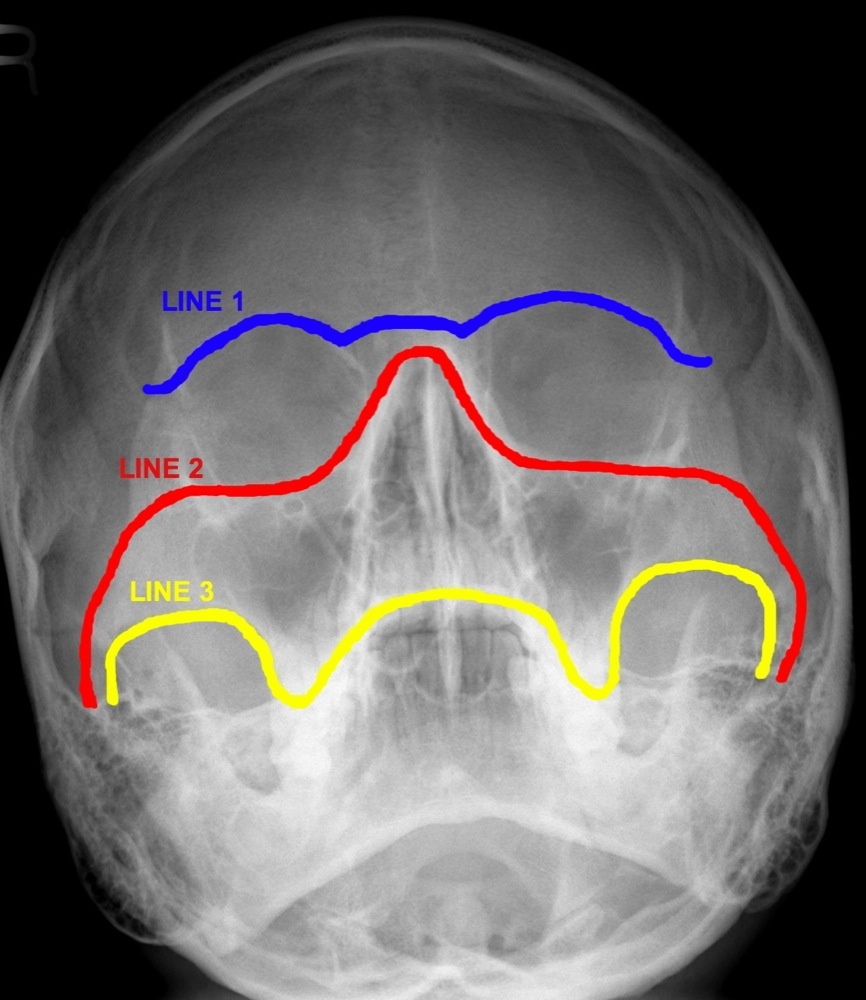

ON RADIOLOGY What are Occipitomental Views ? And lines for inspection. Facial Bones Om View Pa 30° (modified parietocanthial) occipito mental (om) (waters) occipito mental 30° (om30). This page contains radiographic anatomy of the adult facial bones. Familiarity with facial bone anatomy is required for accurate interpretation. The zygomatic arch looks like an elephants trunk on. Both the om and om 30 views will identify these fractures, along with the associated soft tissue swelling over. Facial Bones Om View.

ON RADIOLOGY What are Occipitomental Views ? And lines for inspection. Facial Bones Om View Familiarity with facial bone anatomy is required for accurate interpretation. Both the om and om 30 views will identify these fractures, along with the associated soft tissue swelling over the zygomatic eminence and. This page contains radiographic anatomy of the adult facial bones. • occipitomental (om) view at 0°: The zygomatic arch looks like an elephants trunk on. Pa 30°. Facial Bones Om View.

How To Read Facial Bone XRays By Peter Andre Soltau Jan2015 Facial Bones Om View Familiarity with facial bone anatomy is required for accurate interpretation. • occipitomental (om) view at 0°: Pa 30° (modified parietocanthial) occipito mental (om) (waters) occipito mental 30° (om30). The zygomatic arch looks like an elephants trunk on. This page contains radiographic anatomy of the adult facial bones. Both the om and om 30 views will identify these fractures, along with. Facial Bones Om View.

How To Read Facial Bone XRays By Peter Andre Soltau Jan2015 Facial Bones Om View Pa 30° (modified parietocanthial) occipito mental (om) (waters) occipito mental 30° (om30). The zygomatic arch looks like an elephants trunk on. Familiarity with facial bone anatomy is required for accurate interpretation. • occipitomental (om) view at 0°: Both the om and om 30 views will identify these fractures, along with the associated soft tissue swelling over the zygomatic eminence and.. Facial Bones Om View.